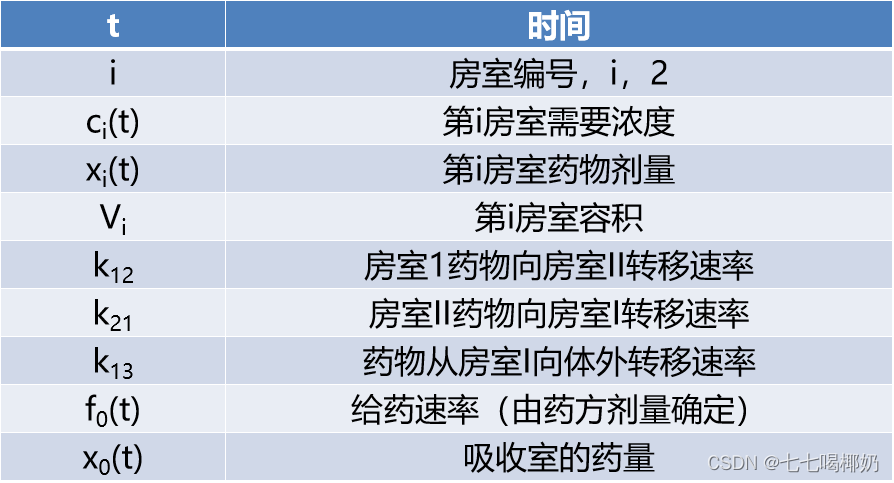

【符号说明】

图14 详细的二房室模型